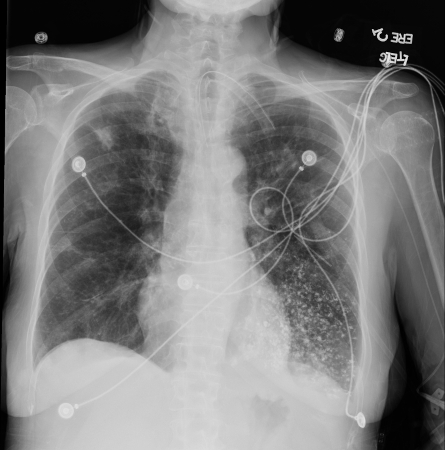

[Figure caption and citation for the preceding image starts]: A. Radiografia torácica portátil ortostática antes da aspiração; B. Radiografia torácica 1 hora após a aspiração, mostrando infiltrados alveolares difusos bilaterais, piores nas bases do lado direitoDo acervo de Dr. Henri Colt [Citation ends].